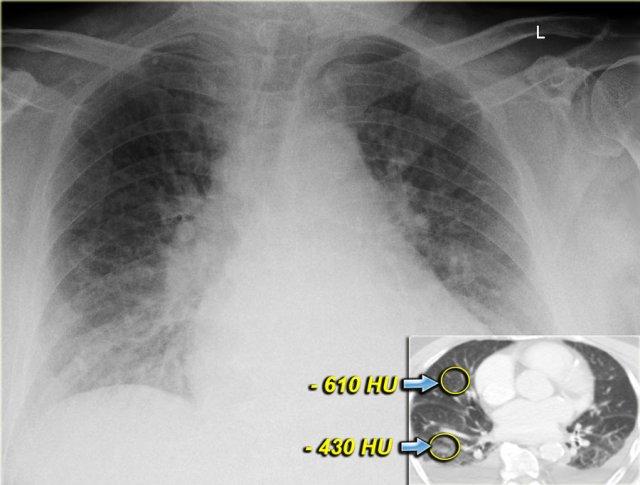

Cả trên X-quang ngực lẫn trên CT, phù nề đều phụ thuộc vào trọng lực và sự chênh lệch tỷ trọng có thể được đo lường.

Lưu ý rằng ngay cả trong mỗi thùy phổi, cũng có sự chênh lệch tỷ trọng phụ thuộc trọng lực.

Điều này chỉ được thấy khi các đông đặc là kết quả của dịch thấm như trong suy tim sung huyết.

Điều này không được thấy khi các đông đặc là kết quả của dịch tiết do nhiễm trùng, máu do xuất huyết, hoặc khi có rò rỉ mao mạch như trong hội chứng suy hô hấp cấp tiến triển (ARDS).